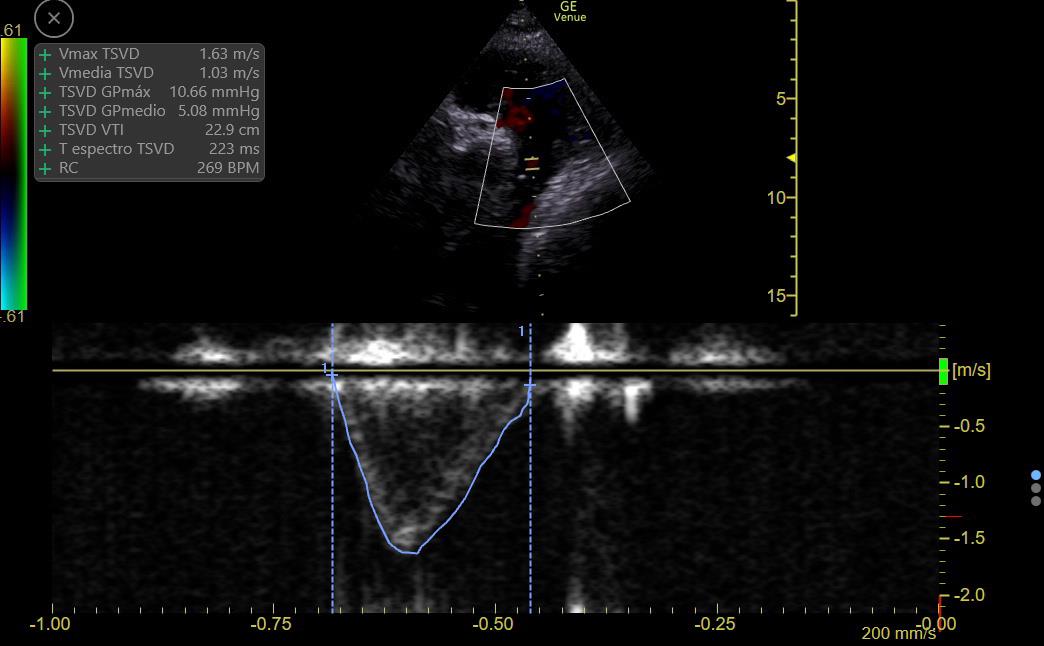

CO can be estimated by measuring flow at the LV or RV outflow tract:

RVOT Doppler shows ⬇️ VTI (9 to 14), so CO is LOW

There is ⬆️ respiratory variation: Low preload vs RV failure or Interdependence (Both Ruled out on #echofirst)

This suggests a low preload state